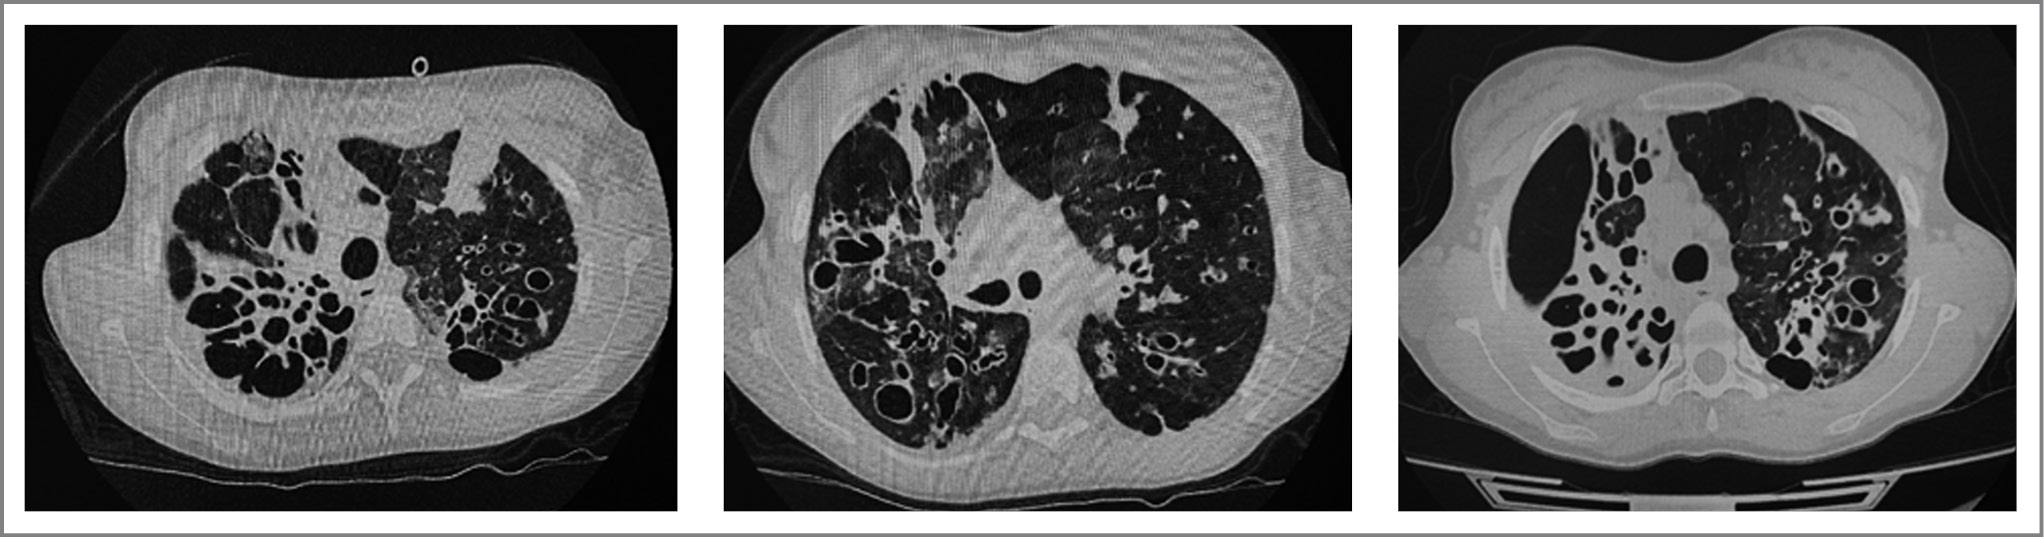

Рентгенография ОГК – R-картина может соответствовать двусторонним бронхоэктазам, кистозным изменениям легких (рис. 2).

Рис. 2. Врожденные бронхоэктазы. Кистозные трансформации легких.

Fig 2. Congenital bronchiectasis. Cystic transformations of the lungs.